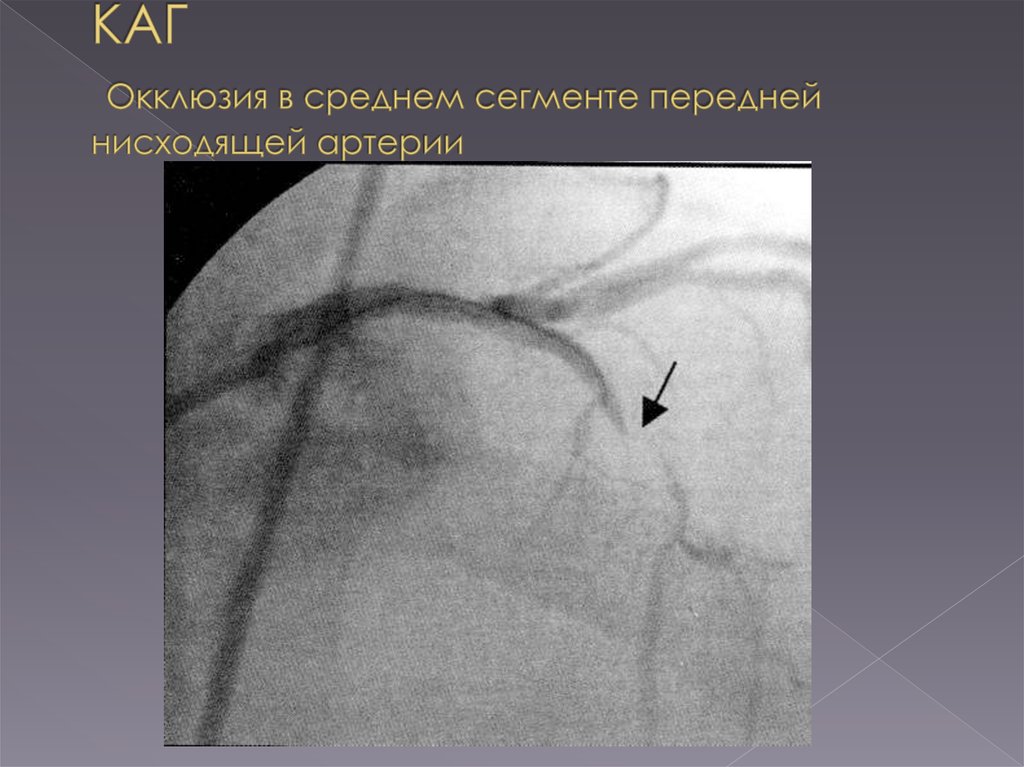

Хроническая окклюзия артерий: причины, симптомы и лечение